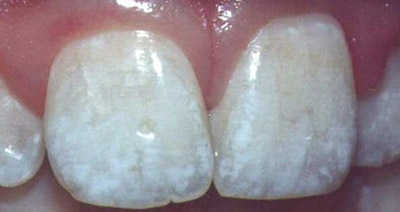

Фото эрозивной, эндемической, штриховой формы

Фото 3. Штриховая форма флюороза, эмаль слегка пятнистая, с несильно выраженными бороздками.